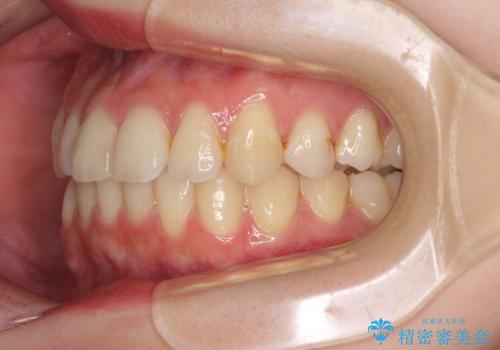

- 上下前歯のデコボコを気にして来院された患者様です。

以前矯正をした後戻りということで、歯列不正はそれほど大きくなかったため、インビザライン・ライトを用いて矯正治療を行うこととしました。

インビザラインは1日に22時間を目安に装着していただきますが、装着時間が十分でないとシミュレーション通りに動かないことがあります。

前歯のデコボコが残っており、シミュレーション通りに動いていない部分がありましたが、再矯正であることやご本人の満足いくところまでデコボコが改善されたとのことで、治療を終了することとしました。